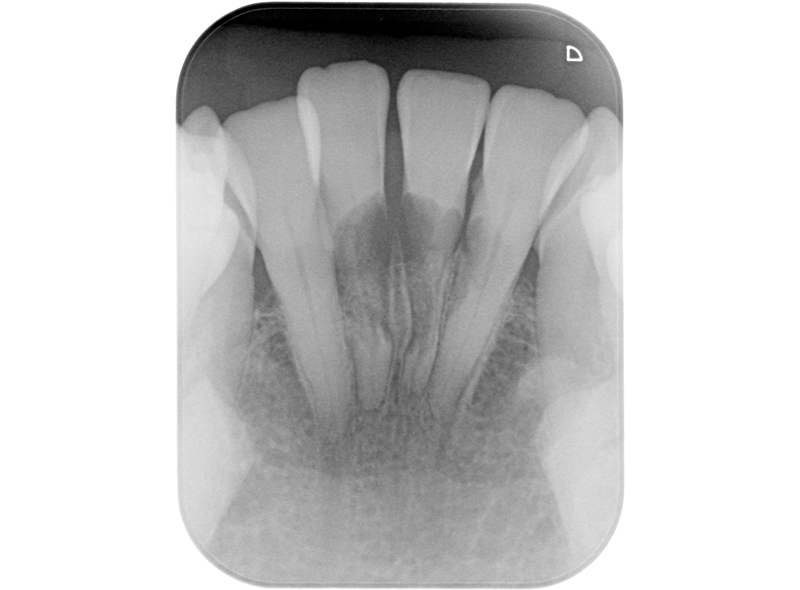

侵襲性歯頚部吸収・歯根吸収

After

| 治療内容 | 6年前にサバイバルゲームでBB弾が歯に当たり、歯が欠けた。 歯髄診査では、11,21ともにEPT+、Cold+。11は侵襲性歯頚部吸収、21は内部の炎症性吸収と診断。また、11にはパーフォレーションも認めた。 21は根管治療、ダイレクトボンディングにて対応。 11は、歯冠部の審美に対してはダイレクトボンディングにて対応。 まず侵襲性歯頚部吸収による吸収部を粘膜剥離しバイオデンティンにて外部より封鎖。後日、パーフォレーション部をバイオデンティンにて根管内部よりリペア。歯髄は正常と診断したが、予防的に根管治療を行うこととした。歯冠部からのアクセスが困難だったため、逆根管治療(歯根端切除術)にて対応。 |